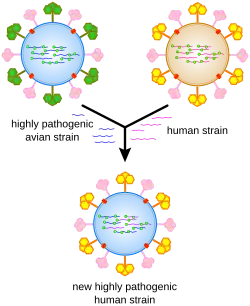

A gripe propaga-se globalmente em ciclos sazonais de epidemias, as quais provocam anualmente entre três e cinco milhões de casos graves da doença e entre 250 000 e 500 000 mortes,[14] número que pode ascender a milhões em anos de pandemia. Ao longo do século XX ocorreram três pandemias de gripe, cada uma delas provocada pelo aparecimento de uma nova estirpe do vírus em seres humanos, e responsáveis pela morte de dezenas de milhões de pessoas. Em muitos casos, as novas estirpes de gripe aparecem quando um vírus já existente se propaga para o ser humano a partir de outra espécie animal, ou quando uma estirpe humana recolhe novos genes de um vírus que só infeta aves ou suínos. Uma estirpe aviária denominada H5N1 levantou algumas preocupações em relação a uma nova pandemia de gripe em finais da década de 1990, mas não chegou a evoluir para uma forma de fácil contágio entre o ser humano.[15] Em abril de 2009 ocorreu uma pandemia de uma nova estirpe que combinava genes da gripe humana, aviária e suina, denominada H1N1 ou gripe suína.[16]

Devido à ausência de enzimas com mecanismos de verificação (proofreading), a ARN polimerase ARN-dependente que copia o genoma viral comete um erro a cerca de cada dez mil nucleótidos, o que corresponde ao comprimento aproximado do ARN viral da gripe. Desta forma, a maioria dos vírus de gripe que são fabricados são mutantes, o que causa deriva antigénica, uma pequena alteração nos antígenos da superfície viral ao longo do tempo.[63] A separação do genoma em oito segmentos distintos de ARN viral permite a mistura ou reagrupamento dos ARN virais, no caso de uma célula ser infectada por mais de um tipo de vírus. A rápida alteração de genética viral resultante provoca mudanças antigénicas, que são alterações súbitas de um antígeno para outro. São estas alterações súbitas e significativas que permitem aos vírus infetar novas espécies de hospedeiros ao mesmo tempo que rapidamente ultrapassam qualquer imunidade. Isto é uma das principais causas da existência de pandemias.[53]

Os vírus de gripe evoluem continuamente, através de mutação ou recombinação.[36] As mutações podem provocar pequenas alterações nos antígenos hemaglutinina e neuraminidase na superfície do vírus. Estas alterações denominam-se deriva antigénica, a qual vai lentamente criando uma cada vez maior variedade de estirpes até que se desenvolva uma que seja capaz de infetar pessoas imunes às estirpes anteriores. Esta nova variante substitui então as anteriores, à medida que se propaga rapidamente entre a população humana, muitas vezes causando uma epidemia.[150] No entanto, uma vez que as estirpes produzidas por deriva genética ainda têm algumas semelhanças com as estirpes mais antigas, algumas pessoas continuam a ser imunes. Por outro lado, quando os vírus de gripe se recombinam adquirem antígenos completamente novos, um processo que é denominado mudança antigénica. Se for produzido um vírus de gripe humano com antígenos completamente novos, toda a população estará susceptível e o novo vírus dissemina-se de forma incontrolável, dando origem a uma pandemia.[151] No entanto, tem também vindo a ser proposta uma abordagem alternativa a este modelo de pandemia baseado em mudanças e derivas antigénicas, o qual sustenta que as pandemias periódicas são produzidas pelas interações de um conjunto fixo de estirpes humanas, sendo a população humana que ciclicamente adapta a sua imunidade às diferentes estirpes desse conjunto.[152]